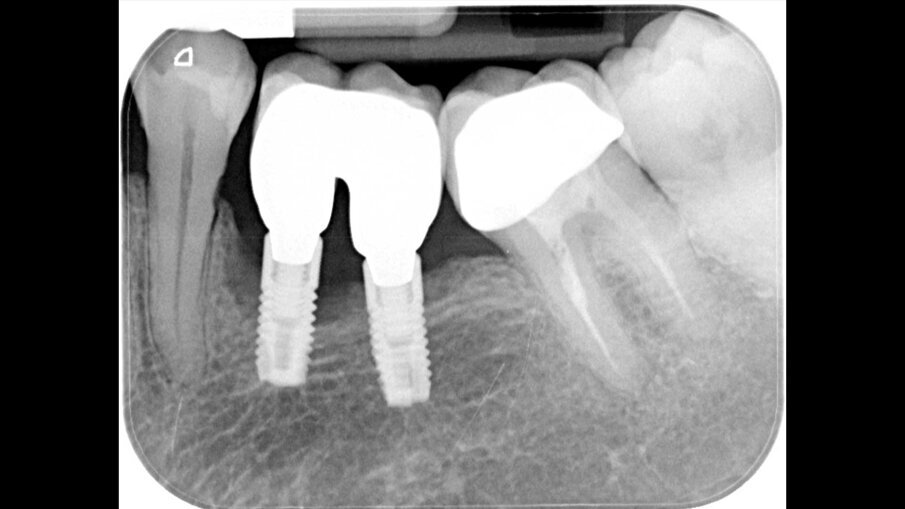

Dopo 3 mesi i tessuti molli appaiono sani e senza segni di infiammazione, con un adeguato tragitto transmucoso (Figg. 7, 8). Alla visita di follow-up a 1 anno il paziente presenta una risoluzione della malattia perimplantare e l’esame radiografico conferma il riempimento del difetto angolare (Fig. 9).

Fig. 9 - La radiografia di controllo ad un anno dal trattamento evidenzia il riempimento del difetto angolare.